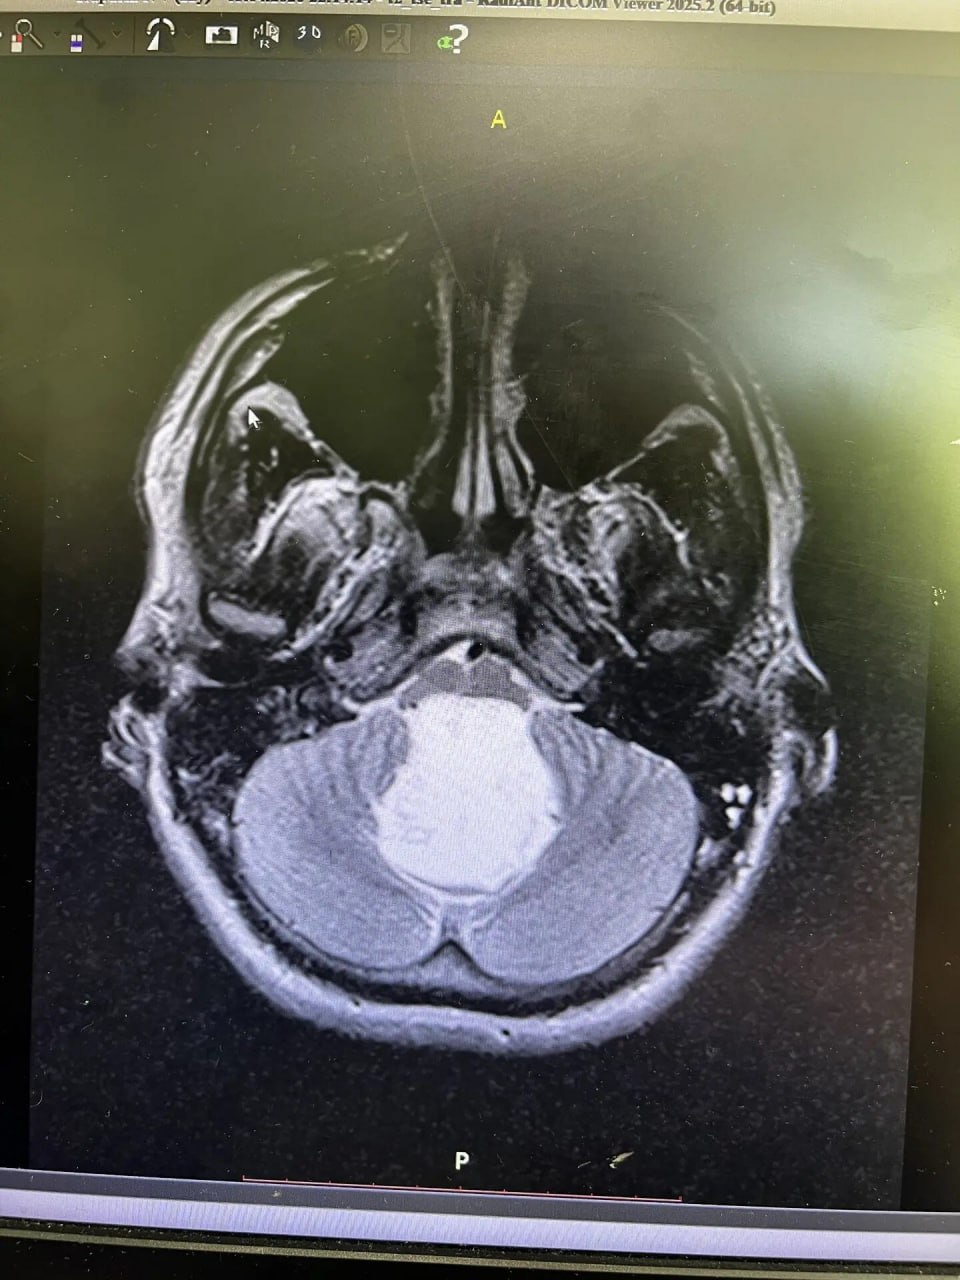

Никита был обычным крепким парнем: спорт, армия — причем в элитные войска, куда каждого второго не берут. Первые легкие головные боли появились еще в 2024-м, но кто на них обращает внимание в таком возрасте? К 2025-му голова разламывалась уже всерьез, но стандартные обследования ничего не показывали. А в апреле 2026-го стало совсем плохо: боль была невыносимая, ноги не слушались. Решающим стало упрямство отца — фельдшера «скорой» с тридцатилетним стажем. Он заставил сына сделать МРТ. Нейрохирурги сначала глазам не поверили: опухоль расползлась почти на 6 на 4,5 сантиметра и намертво передавила дыхательный центр мозга. Ещё сутки промедления — и всё.

Пациента прямо с консультации повезли на операционный стол. Семь часов нейрохирурги Шалиндер Аул и Ильяс Кылданов ювелирно убирали зловредную «жемчужину». По словам хирургов, такая патология встречается у трёх-девяти человек на сто тысяч. А с такими гигантскими размерами — это вообще третья ласточка за двадцать лет практики.